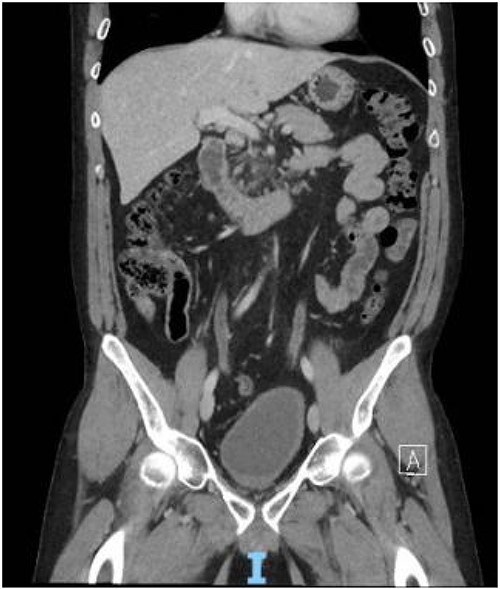

In contrast to the prior biopsies, the resection specimen revealed the tumor harbored areas with marked nuclear atypia, high cellularity, mitoses, and necrosis. A diagnosis of poorly differentiated leiomyosarcoma was rendered, with margins free of tumor (closest was 2 mm) (Fig. 3). The patient had an uneventful recovery. He reported complete resolution of his obstructive symptoms 1 month after the procedure. Given his recent diagnosis of high-grade cancer, adjuvant conventional fractionation radiotherapy targeting the postoperative bed without any elective nodal coverage was undertaken. Two months after radiotherapy, he reported having a normal urinary stream, good erections with penetration and forward ejaculation. He has now been on follow-up for the past 24 months with six monthly CT scans with no evidence of recurrence (Fig 4).

Contrast CT pelvis at 20 months post-surgery showing no residual disease.